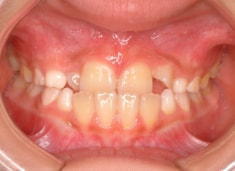

治療前

FX(フェイシャルアキシス)は85度なので東洋人の平均値に近く、下顎が前方に過剰成長するリスクは強くはありません。

しかしやはり上顎は劣成長で、下顎が優位な状態ではあります。

上下顎のギャップはありますが、顔面自体の幅径は良好な値を示していますので、スペース不足は拡大することによって解決できポテンシャルはあると考えられます。

左右の非対称もさほど強くありません。

骨年齢は実年齢よりも低めなので、今後下顎の旺盛な成長が見込まれます。